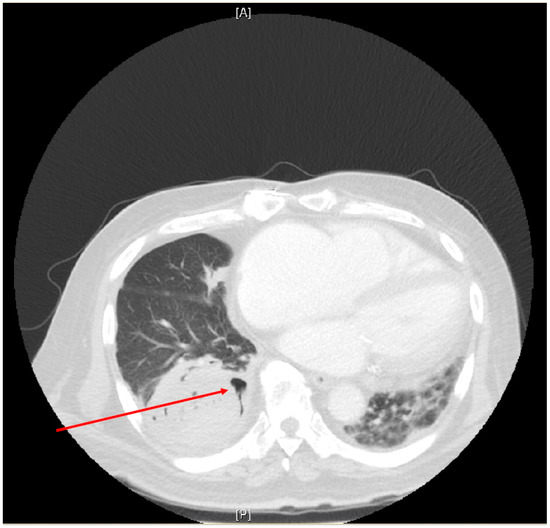

| RADIOLOGY (typical or more common abnormalities on chest CT) | Peripheral, bilateral GGO +/− consolidation or visible intralobular lines (i.e., crazy paving) in early stages. Multifocal GGO (round) +/− consolidation or intralobular lines at peak stage. Reverse halo sign +/− organising pneumonia at late stage ** | As directed by clinical findings; organ involvement rare | Diffuse GGO Interstitial infiltrates (predominantly upper lobes and perihilar regions) | Nodules (1 or more) Cryptococcomas, Pulmonary infiltrates | Focal or diffuse airspace disease Upper lobe cavitation thick-walled bullae, lymphadenopathy | Similar to CAM and CAPA | GGO, mass lesions +/− cavitation Consolidation, Reverse halo sign may be present. ## | |